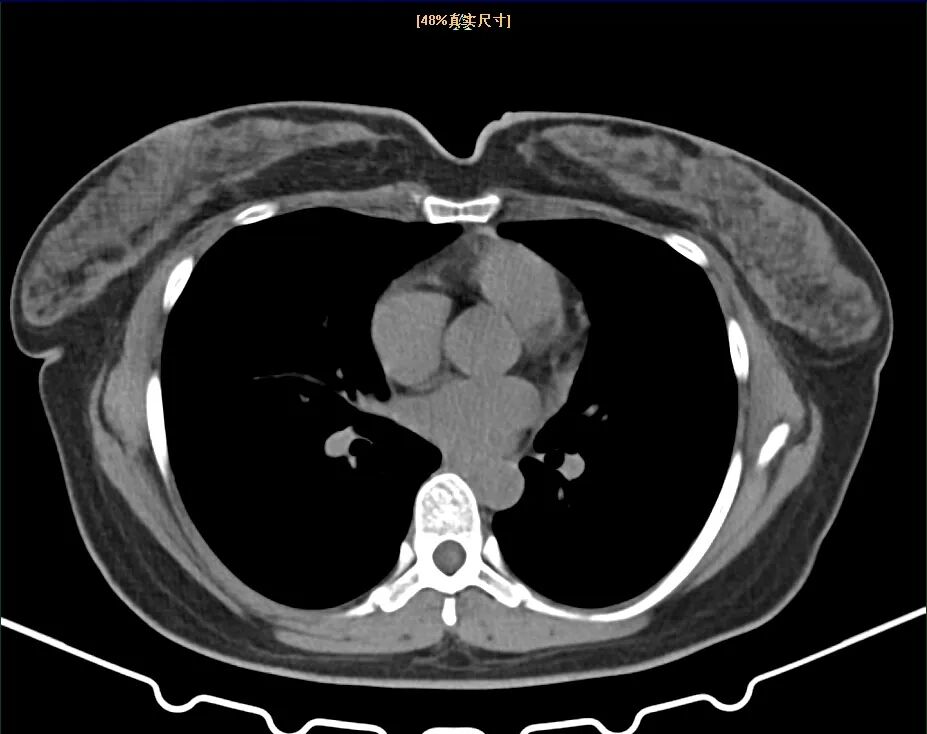

来到义乌市中心医院医学美容中心,科主任虞宏纲为沈女士进行了详细的检查和评估。检查发现,沈女士的双侧乳房明显肥大、下垂,乳房下极超过乳房下皱襞达10厘米以上,乳头位于乳房下皱襞以下,属于典型的巨乳症。

“巨乳症是指女性乳房过度发育,体积异常增大,超过体重的3%左右。它不仅影响体型美观,更重要的是会给患者带来一系列身心问题。”虞宏纲解释,巨乳症患者常常伴有肩背酸痛、乳房下皱襞湿疹、甚至脊柱后突等问题,很多患者因此产生自卑、焦虑等心理问题,严重影响生活质量。

目前巨乳症的治疗方法主要是手术治疗,即巨乳缩小整形术。这种手术通过切除部分乳房组织,重新塑形,使乳房恢复到正常大小和形态,但手术难度较大,对医生的技术要求很高,既要考虑切除的量和形状,又要保证乳头乳晕的血供和感觉,还要兼顾双侧对称性和术后美观度。